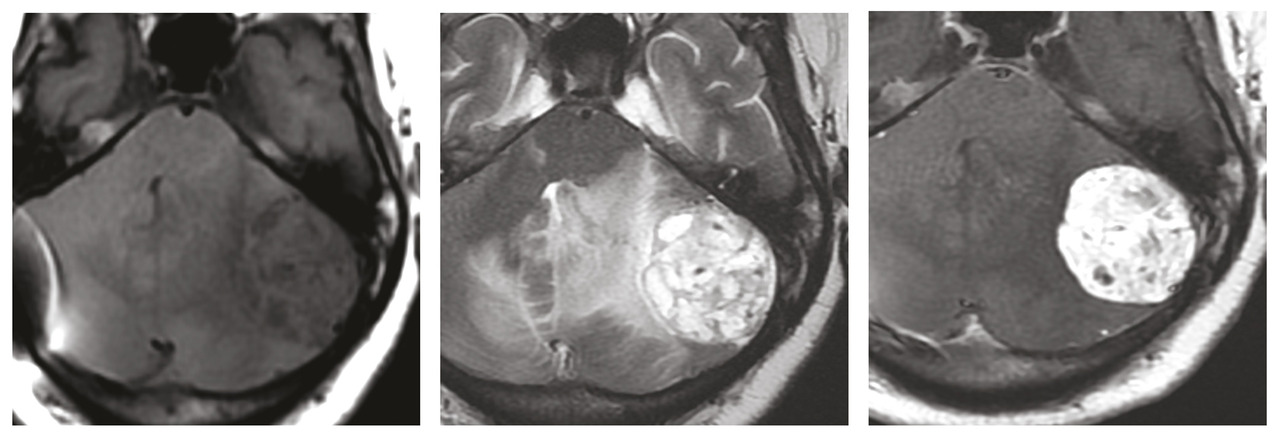

Une femme de 32 ans, sans antécédents pathologiques, consulte pour baisse brutale de l’acuité visuelle. L’examen ophtalmologique trouve un œdème papillaire bilatéral, le reste de l’examen neurologique est sans particularités. Face à cette symptomatologie, un scanner cérébral est réalisé en urgence. Il montre un processus cérébelleux gauche responsable d’un effet de masse sur le quatrième ventricule avec une hydrocéphalie d’amont et des signes de résorption transépendymaire (fig. 1 ). Par la suite, la patiente a bénéficié d’une dérivation ventriculo-péritonéale. Une imagerie par résonance magnétique (IRM) cérébrale a été réalisée pour une meilleure analyse. Elle a permis d’objectiver un processus intra-axial cérébelleux gauche bien limité à double composante kystique et charnue majoritaire en hyposignal T1-hypersignal T2 sans restriction sur la diffusion et se rehaussant de façon intense après injection de chélates de gadolinium (fig. 2 ). La patiente a été opérée (résection en monobloc de la tumeur) (fig. 3 ). Le diagnostic d’hémangioblastome a été confirmé à l’examen anatomopathologique. La patiente s’est améliorée par la suite sur le plan neurologique mais elle a conservé une cécité définitive.

Une IRM de contrôle réalisée deux mois après le geste opératoire montre des stigmates hémorragiques sans résidu tumoral.

Le traitement standard consiste en l’exérèse chirurgicale des tumeurs surtout de la fosse cérébrale postérieure (FCP) qui doivent être traitées rapidement du fait de leur potentiel de croissance rapide.2 La chimiothérapie n’est pas validée.